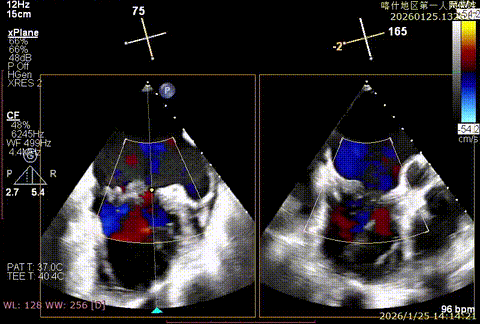

该例患者为DMR类Barlows患者,二尖瓣重度反流,患者1,2,3区均可见脱垂,脱垂主要源于3区,反流主要源于3区。术前制定手术策略:使用一把XTR解决患者瓣叶脱垂与二尖瓣反流。术中进行房间隔穿刺后将XTR-CDS送入左心房,通过操控“M”旋钮,成功将二尖瓣夹定位于2区正上方。在2区进行弹道测试成功后,进行Orientation调整。在3区将二尖瓣夹送入左心室,成功捕捞和夹持瓣叶后缓慢关紧夹臂,解决大部分反流,Saide by Saide L植入第二把XTR。TEE检查见二尖瓣反流程度充分降低至1+,二尖瓣双孔组织桥稳定,跨瓣压差3mmHg,肺静脉逆流改善明显,手术安全结束。

X-plan切面3区后叶脱垂

X-plan切面重度反流